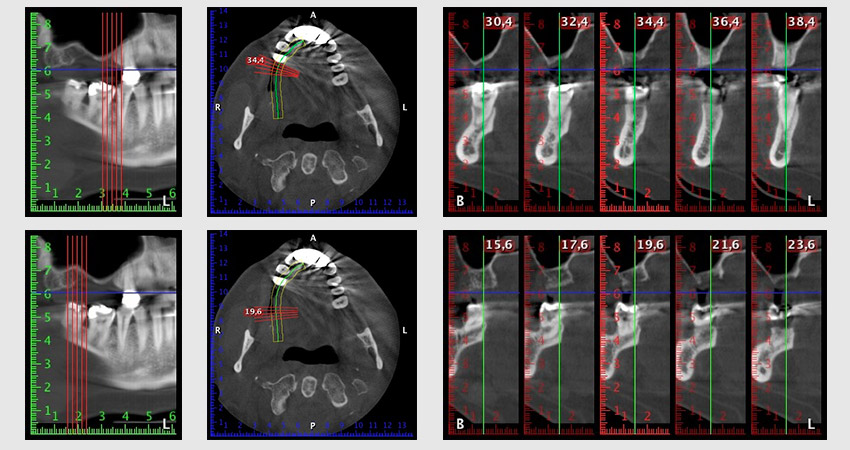

Etwa sechs Monate nach Extraktion der Zähne 16 und 14 wurde zur Planung und Risikominimierung eine digitale Volumentomografie (DVT, Planmeca) erstellt. Hierbei wurde deutlich, dass der Knochen sich nicht in der gewünschten Quantität regeneriert hat (Abb. 2 bis 7).

Abb. 2 bis 7: DVT mit stark reduziertem horizontalen Knochenangebot.

Um die Augmentation auf Regio 14 einzuschränken, wurde in Absprache mit der Patientin eine Schrägstellung des Implantats 16 nach dorso-kranial geplant (Abb. 8).

Abb. 8: DVT mit Planung des Insertionswinkels für das Implantat 16.